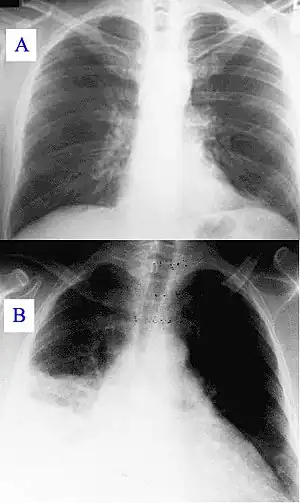

| A) Normal chest radiograph; B) Q fever pneumonia affecting the right lower and middle lobes. Note the loss of the normal radiographic silhouette (contour) between the affected lung and its right heart border as well as between the affected lung and its right diaphragm border. This phenomenon is called the silhouette sign | |